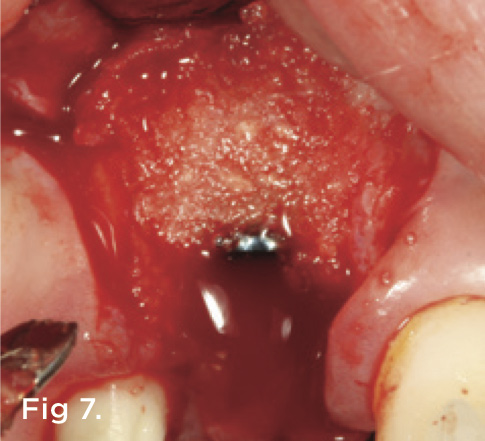

A 38-year-old Caucasian female patient presented with a high smile line and loss of the papilla between tooth No. 7 and edentulous adjacent site No. 8 (Figure 1). Understandably, the patient was unhappy and embarrassed about her esthetic condition. Her dental history revealed tooth replacement of No. 8 with an implant that eventually failed. The site had been previously bone grafted upon implant removal. She was given a composite pontic No. 8 bonded to a tooth No. 7 composite veneer as a transitional restoration. The implant was positioned too close to the proximal surface of tooth No. 7, which stripped the periodontal attachment of the root and ultimately caused loss of the papilla (Figure 2). As previously outlined, the treatment sequence would be to first provide a provisional restorative solution to evaluate the projected outcomes and assess if the patient was willing to undergo orthodontic therapy. In this situation, a full-coverage crown No. 7 with a cantilevered pontic No. 8, with artificial acrylic gingiva to replace the lost papilla on the mesial aspect of tooth No. 7 was used as a transitional temporary prosthesis (Figure 3). In addition, a composite resin restoration was placed on the mesial aspect of tooth No. 9 to restore its individual tooth proportion and shape. The patient’s esthetic outcome could now be evaluated with restorative correction alone; it was therefore mutually determined that the correction of her deformity would best be served with additional orthodontic forced eruption therapy. A fixed orthodontic appliance (brackets) was bonded to the teeth and temporary prosthesis. The level of the interproximal pink acrylic was used as a therapeutic guide for the amount of forced eruption required as well as the alignment of the mesial papilla of No. 7 to that of the adjacent papillae height (Figure 4). Floss was used to elevate the amount of vertical movement achieved relative to the adjacent papilla tooth No. 9. Eventually, all the artificial pink acrylic was removed. (Note that the distal papilla on tooth No. 7 also comes more incisal—in fact, it is slightly excessive at the endpoint of treatment [Figure 5]). However, the distal papilla and midfacial tissues of tooth No. 7 can be reshaped through clinical crown lengthening toward the end of treatment prior to definitive restoration, thereby restoring the proper papilla height-to-tooth ratio of 40%. After stabilization of tooth No. 7 for a minimum of 6 months post-orthodontics, an implant was placed in site No. 8. A papilla-sparing incision design was used for flap elevation (Figure 6), bone allograft was used to further augment the facial aspect of the ridge simultaneously with implant placement (Figure 7), and a resorbable membrane was used for guided bone regeneration.

Fig 7. A bone allograft was placed to augment the labial aspect of ridge No. 8 during simultaneous implant placement.

Figure 7